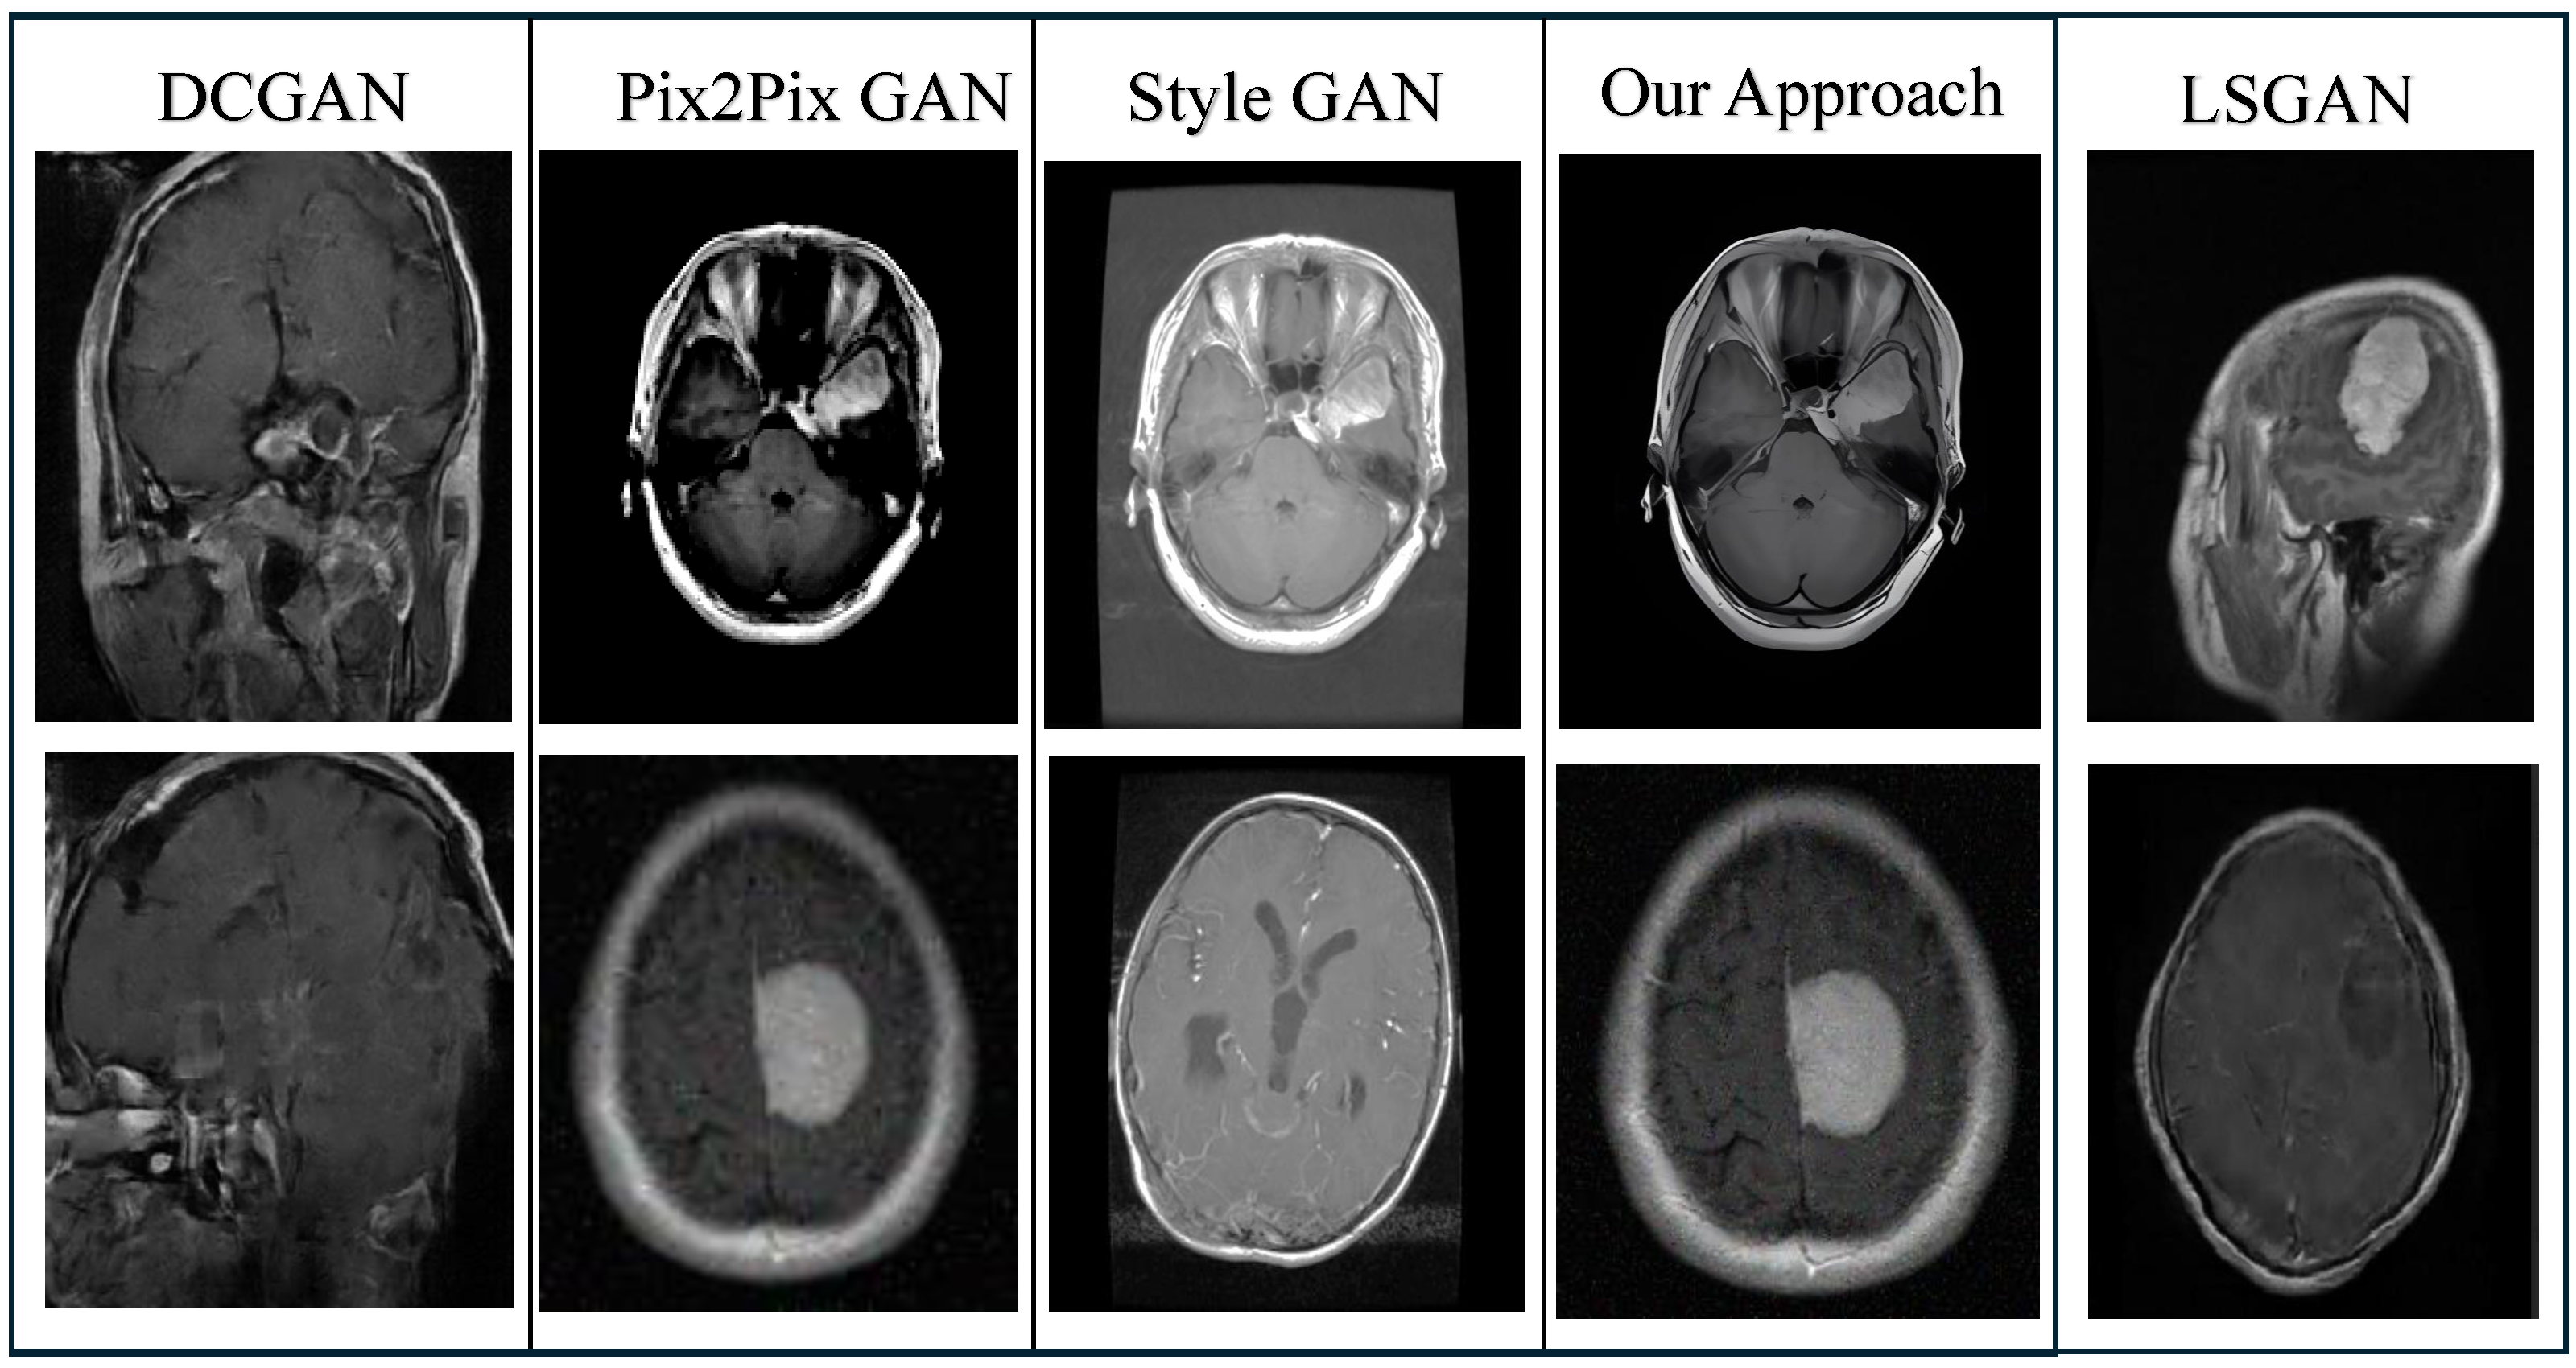

- A comprehensive evaluation was performed on a range of state-of-the-art models, including our proposed PixMed-Enhancer approach, to analyze their performance metrics.

| Dataset | GAN Model | Accuracy (%) | Loss | Recall |

|---|---|---|---|---|

| Pix2pix [41] | 97.87 | 0.0751 | 0.97 | |

| DCGAN [40] | 96.05 | 0.0983 | 0.95 | |

| [43] | StyleGAN [42] | 98.61 | 0.0554 | 0.97 |

| LSGAN [30] | 95.13 | 0.0882 | 0.95 | |

| Our Approach | 99.07 | 0.0458 | 0.98 | |

| Pix2pix [41] | 87.67 | 0.1151 | 0.87 | |

| DCGAN [40] | 85.03 | 0.1243 | 0.84 | |

| [39] | StyleGAN [42] | 88.54 | 0.1003 | 0.88 |

| LSGAN [30] | 84.32 | 0.1681 | 0.83 | |

| Our Approach | 89.58 | 0.0958 | 0.89 |